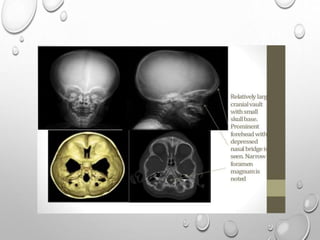

RADIOLOGY

HEAD

LARGE CRANIUM , THOUGH DECREASED AP DIAMETER –

BRACHYCEPHALY

NARROW FORAMEN MAGNUM

SHORT BASE OF SKULL

BASILAR IMPRESSION

FACE

FRONTAL BOSSING

DEPRESSED NASAL BRIDGE

NORMAL MANDIBLE ,SO IMPRESSION OF PROGNATHISM

SKULL

IN INFANCY DELAYED OR ABSENT OSSIFICATION OF CALVARIA

MULTIPLE WORMIAN BONES

WIDENING OF PRIMARY SUTURES – HOT CROSS BUN SIGN

SUPRAORBITAL , TEMPORAL SQUAMA , OCCIPITAL REGION ARE THICKENED

DEFORMED , ENLARGED FORAMEN MAGNUM

SMALL , UNDERDEVELOPED FACIALBONES

HYPOPLASTIC SINUS

NASAL BONE FAIL TO OSSIFY

SMALL MAXILLA , LARGE MANDIBLE

DELAYED , DEFECTIVE DENTITION